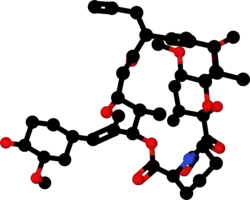

Chemically, it is a macrolide lactone[8] that was first discovered in 1987, from the fermentation broth of a Japanese soil sample that contained the bacterium Streptomyces tsukubensis.

Tacrolimus is a macrolide calcineurin inhibitor. In T-cells, activation of the T-cell receptor normally increases intracellular calcium, which acts via calmodulin to activate calcineurin. Calcineurin then dephosphorylates the transcription factor nuclear factor of activated T-cells (NF-AT), which moves to the nucleus of the T-cell and increases the activity of genes coding for IL-2 and related cytokines. Tacrolimus prevents the dephosphorylation of NF-AT.[30]

In detail, tacrolimus reduces peptidylprolyl isomerase activity by binding to the immunophilin FKBP12 (FK506 binding protein), creating a new complex. This FKBP12–FK506 complex interacts with and inhibits calcineurin, thus inhibiting both T-lymphocyte signal transduction and IL-2 transcription.[31] Although this activity is similar to that of cyclosporin, the incidence of acute rejection is reduced by tacrolimus use over cyclosporin use.[10] Although short-term immunosuppression concerning patient and graft survival is found to be similar between the two drugs, tacrolimus results in a more favorable lipid profile, and this may have important long-term implications given the prognostic influence of rejection on graft survival.[32]